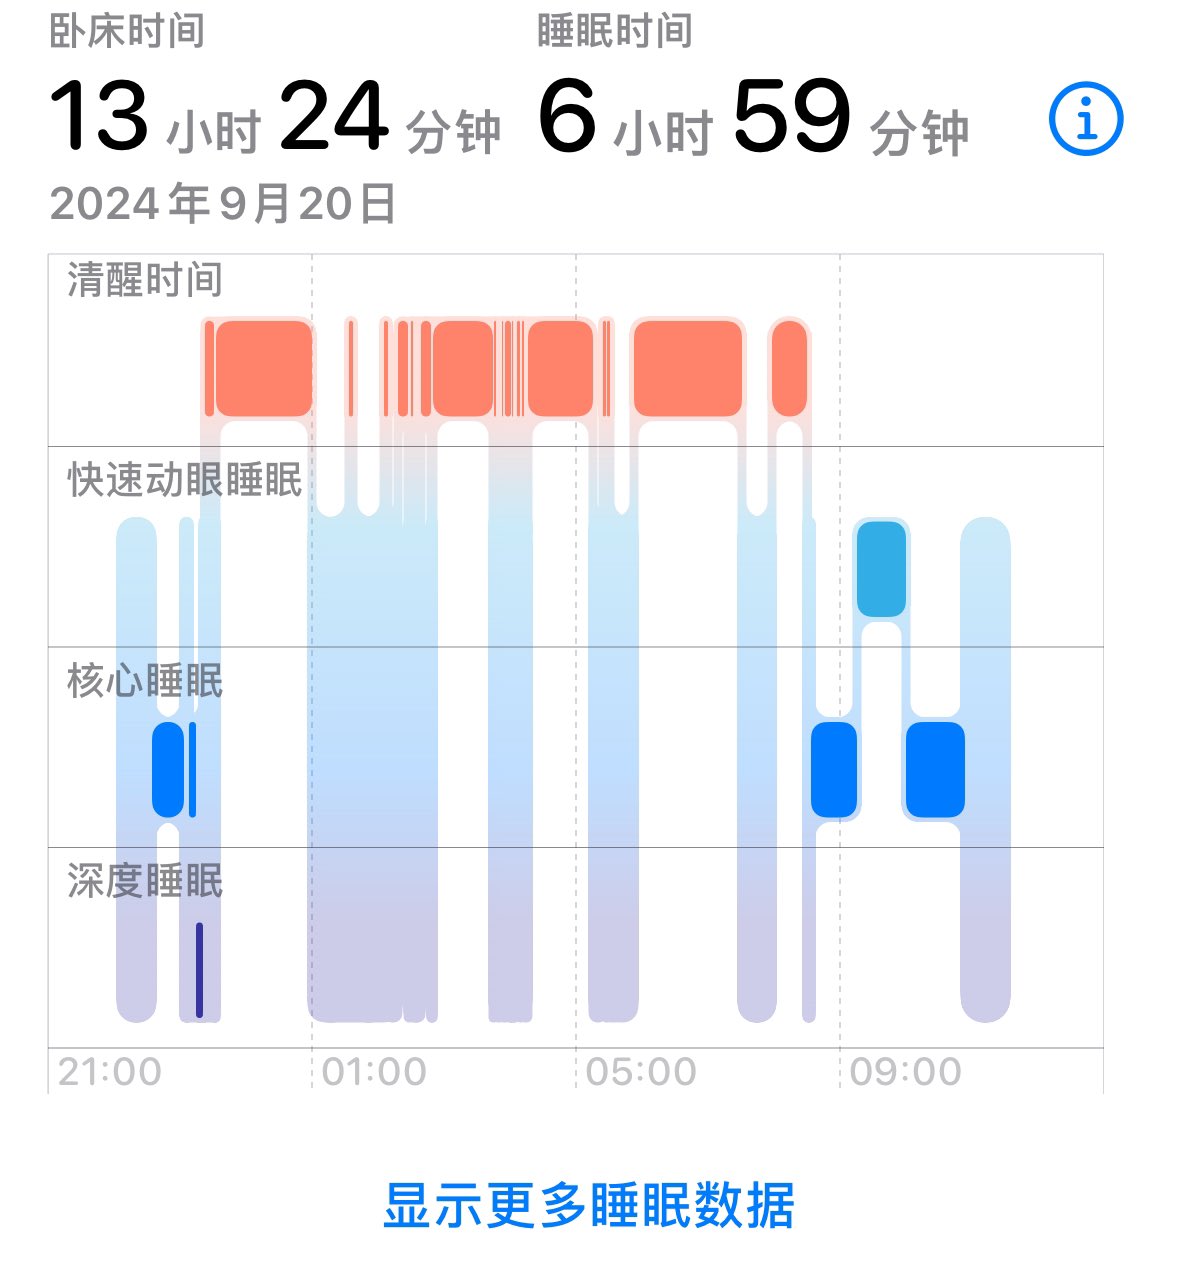

-睡眠障碍:包括严重失眠、REM周期紊乱。

-睡眠障碍:包括严重失眠、REM周期紊乱。

此剂量下对睡眠的改善作用,增加了慢波睡眠且没有影响rem,精力恢复+